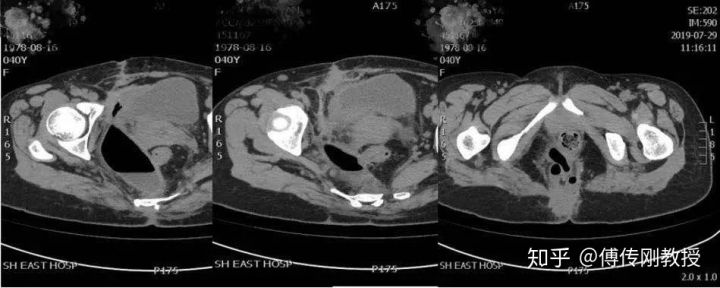

2019.07.29出现直肠和阴道流脓症状,去上海市东方医院求医。做了相关的检查,CT和肠镜结果:盆腔畸胎瘤(经骶切除术后);直肠骶尾瘘;盆腔脓肿。

入院腹部CT